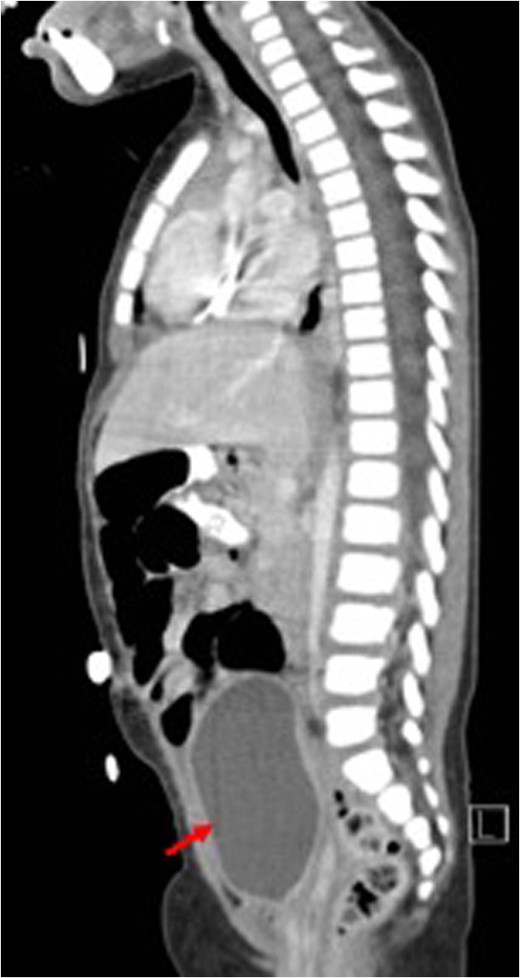

Sagittal view (CT) for the mass (white arrow) post-chemotherapy showing reduction in size (red arrow) bladder.

Total abdominal hysterectomy, bilateral salpingectomy with upper vaginectomy.